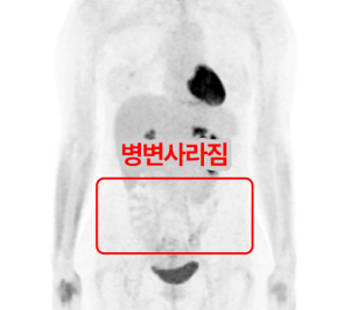

2025.1.16 CT

2025.4.9 CT

※ 동일한 조건에서 촬영된(사진에 대한 별도 조작이 처리되지 않은) 본원에서 진료 및 치료를 받으신 고객(들)의 사진입니다.

사진의 결과는 사례에 기반한 참고 자료로, 개인별 치료 결과는 상이할 수 있습니다.

또한 치료 후에는 홍반, 열감, 피로감, 근육통, 저혈습 등 부작용이 발생할 수 있습니다.